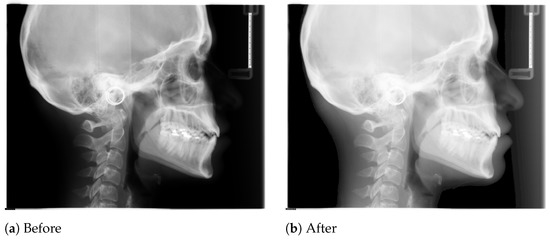

The borders of the soft tissue in the initial X-ray images are not clearly visible due to poor contrast, and hence we need to apply some preprocessing steps, i.e., to use the gamma correction method to sharpen and increase the contrast of the borders of the soft tissue.

In Figure 1, we show a sample X-ray image before and after applying the gamma correction. It is clear that after applying the gamma correction, the soft tissue borders are now visible for further usage. In our tool, we first preprocess all X-ray images using the gamma correction before performing actual annotations.

Figure 1. Effect of gamma correction of a sample X-ray image.